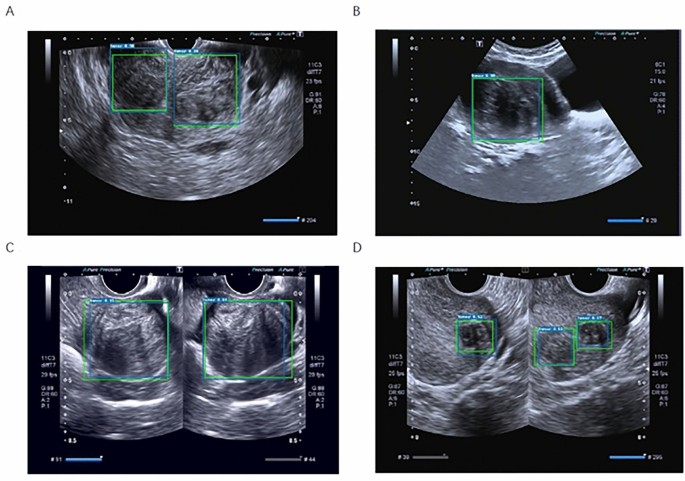

Uterine fibroid detection results. (A) Target detection results of multiple uterine fibroids in a single ultrasound image. (B) Target detection results of a single uterine fibroid in a single ultrasound image. (C) Target detection results of single uterine fibroids in patients with double ultrasound images. (D) Target detection results of multiple uterine fibroids in patients with double ultrasound images. Green boxes are the GT boxes annotated by our invited radiologists, and blue boxes are the boxes predicted by the trained model. The number marked in the upper left corner is the model detection confidence score.